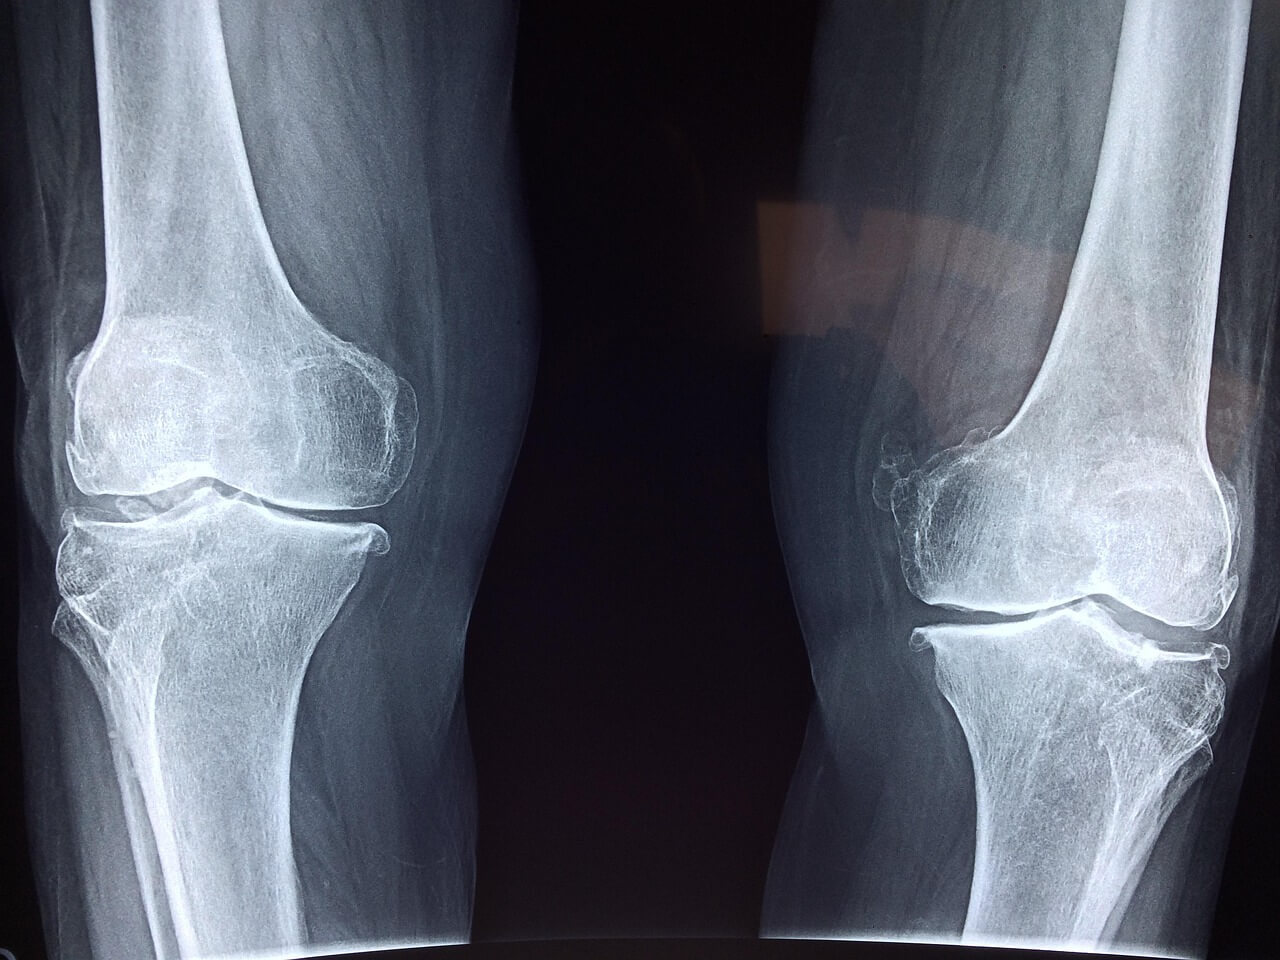

4-2. 영상 검사 (X-ray, MRI)

X-ray 검사에서는 관절 간격이 줄어든 것을 확인할 수 있으며, 진행된 경우 뼈의 변형도 나타납니다. MRI 검사는 연골 손상 정도를 더 세밀하게 파악할 수 있어 조기 진단에 도움이 됩니다. 이러한 검사는 관절염의 진행 정도를 정확히 알 수 있는 중요한 도구이므로 주기적인 검사를 권장합니다.